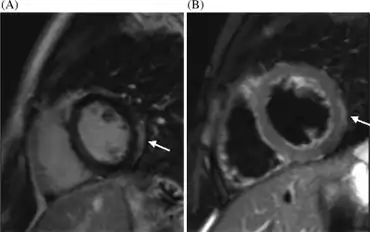

Acute viral myocarditis-a) Oedema of the lateral left ventricle arrow b) high signal intensity of the left ventricle arrow